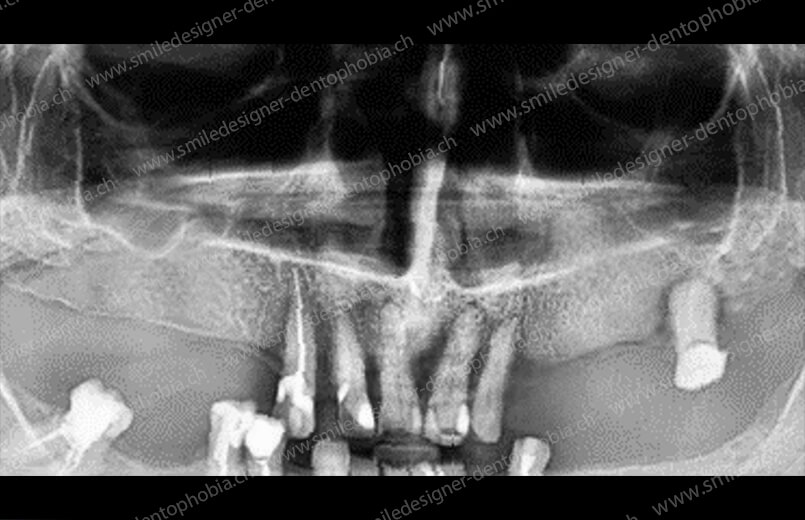

Cas clinique « GOLD STANDARD MCI » bi-maxillaire : Bridge implanto-porté sans extension postérieure (ALL ON 10). Version définitive des bridges avec un cosmétique en céramique.

Cas clinique « GOLD STANDARD MCI » bi-maxillaire : Bridge implanto-porté sans extension (ALL ON 8) au maxillaire et à la mandibule. Version définitive des bridges avec un cosmétique en céramique.

Cas clinique « GOLD STANDARD MCI » maxillaire : Bridge implanto-porté sans extension (ALL ON 8). Version définitive des bridges avec un cosmétique en céramique.

Cas clinique « GOLD STANDARD MCI » maxillaire : Bridge implanto-porté sans extension (ALL ON 10). Version définitive des bridges avec un cosmétique en céramique.

Cas clinique « GOLD STANDARD MCI » bi-maxillaire : Bridge implanto-porté sans extension (ALL ON 10). Version définitive des bridges avec un cosmétique en céramique.

Cas clinique « GOLD STANDARD MCI » bi-maxillaire : Bridge implanto-porté sans extension (ALL ON 8). Version définitive des bridges avec un cosmétique en céramique.